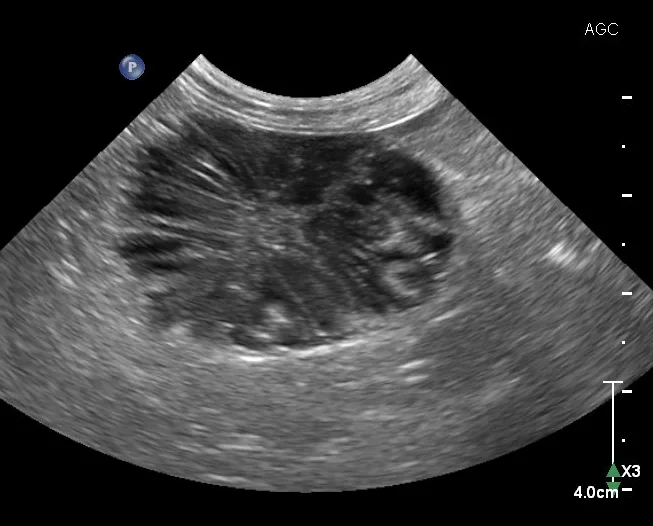

5. Assessment of Gallbladder Mucoceles

The gallbladder is located just to the right of midline between the quadrate and right lateral liver lobes. A normal gallbladder contains anechoic bile and is thin-walled (cats, 1 mm; dogs, ≤2 mm).10,20 In cats, an occasional bilobed gallbladder is normal.10 Bile is normally anechoic, but variably echogenic sludge can accumulate in the gallbladder as suspended particulates or dependent luminal contents.21 Echogenic luminal contents can sometimes be incidental and not associated with biliary disease.21

Dilation or distension of the gallbladder with accumulated hypoechoic mucus may be classified as a gallbladder mucocele but can also be characterized as inspissated bile, mucinous hyperplasia, cystic hyperplasia, and other associated conditions.21 Gallbladder mucoceles are more common in older, small-breed dogs and are rare in cats.21,22 The formation of gallbladder mucoceles is a continuum, starting with echogenic bile, then a stellate pattern, and finally a kiwifruit pattern (ie, a round accumulation of hypoechoic mucus that contains thin, stellate hyperechoic striations; Figure 5).21 Although the exact etiology of mucoceles is controversial, their clinical importance is important, as they can lead to gallbladder rupture, bile peritonitis, and emergency surgery.21

FIGURE 5

A mature gallbladder mucocele with a central hyperechoic area that is heterogeneous with linear hyperechoic striations in a dog. This appearance is often described as a kiwifruit pattern.

Elective cholecystectomy (ie, prior to biliary obstruction or gallbladder rupture) has been shown to have a lower mortality rate than nonelective cholecystectomy (ie, after obstruction or rupture).23 Suspended (ie, not gravity-dependent) mucus and/or hyperechoic bile are both potential indications for cholecystectomy.23

Although mature gallbladder mucoceles are associated with gallbladder enlargement and wall thinning, numerous etiologies (eg, cholecystitis, gallbladder wall edema, cholecystolithiasis, cystic mucosal hyperplasia, neoplasia [rare]) can also lead to gallbladder wall thickening (>3-3.5 mm).10,20 Bile aspiration via ultrasound-guided cholecystocentesis can be performed for bile culture and/or gallbladder decompression10; however, this procedure has increased the risk for bile leakage (and secondary peritonitis) with gallbladder distension or disease of the wall.